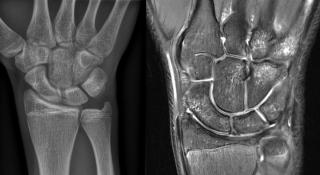

Wat zijn geavanceerde beeldvormingstechnieken bij spier- en gewrichtsklachten? De dienst medische beeldvorming licht indicaties en voordelen toe van het nieuwe MRI-toestel met pseudo-CT, echogeleide infiltraties en PedCAT.